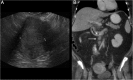

Endometrial cancer is the most common gynaecologic malignancy in developed countries and its incidence is increasing. First-level treatment, if no contraindicated, is based on surgery. Pre-operative imaging is needed for evaluation of local extent and detection of distant metastases in order to guide treatment planning. Radiological evaluation, based on transvaginal ultrasound, MR and CT, can make the difference in disease management, paying special attention to assessment of entity of myometrial invasion, cervical stromal extension, and assessment of lymph nodal involvement and distant metastases.